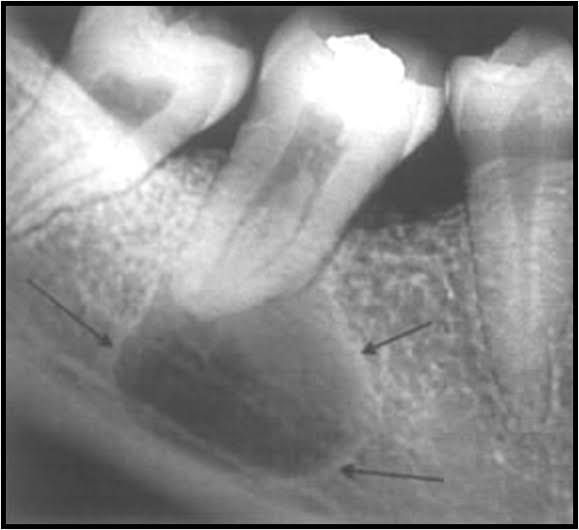

Radicular cyst is an inflammatory jaw cyst originating from epithelial remnants of the periodontal ligament as a result of inflammation that is generally a consequence of pulp necrosis. The resulting cyst commonly involves the apex of the affected tooth